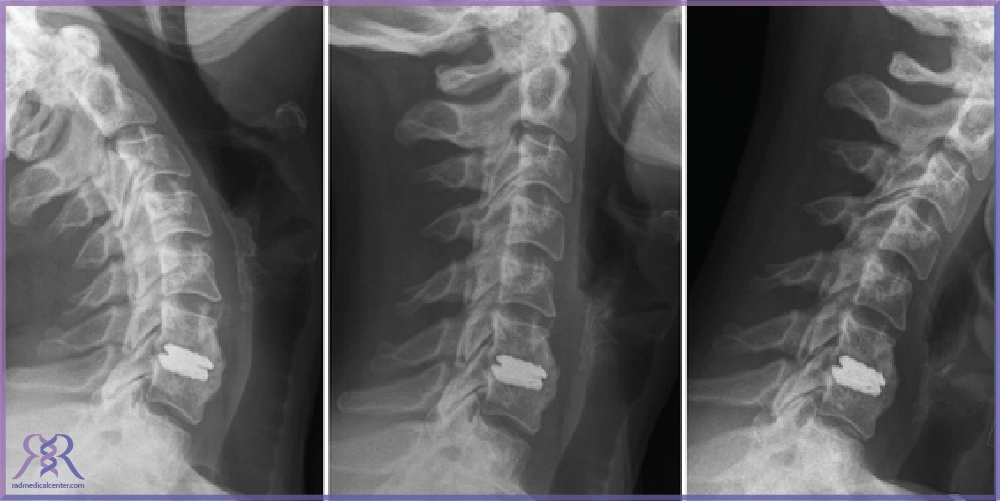

- تستهای تصویربرداری: برای تشخیص دقیقتر از ابزارهای تصویربرداری مانند MRI (تصویربرداری با رزونانس مغناطیسی)، CT (توموگرافی کامپیوتری) و رادیوگرافی (اشعه ایکس) استفاده میشود. MRI بهترین روش برای مشاهده دیسکها و بافتهای نرم است. CT میتواند تصاویر دقیقی از ساختارهای استخوانی گردن ارائه دهد و رادیوگرافی میتواند مشکلات ساختاری مانند تنگی کانال نخاعی را نشان دهد.

از ارزیابیهای اولیه و انتخاب بیمار مناسب گرفته تا بیهوشی، برش کوچک جلوی گردن، خارجسازی دیسک آسیبدیده و جایگذاری دیسک مصنوعی، همهی این مراحل با دقت و استانداردهای بالا انجام میشوند تا بهترین نتیجه حاصل شود. در ادامه، گامبهگام با مراحل جراحی پروتز دیسک گردن آشنا میشویم.

۵. قراردادن پروتز

پس از تخلیه دیسک آسیبدیده، دیسک مصنوعی (پروتز) در فضای خالی بین مهرهها قرار داده میشود. این پروتز طراحی شده تا حرکت طبیعی ستون فقرات را شبیهسازی کند. اندازه و نوع پروتز بر اساس آناتومی دقیق بیمار انتخاب میشود. قرارگیری صحیح آن با کمک ابزارهای تخصصی و تحت دید مستقیم یا تصویربرداری درونعملی انجام میگیرد.